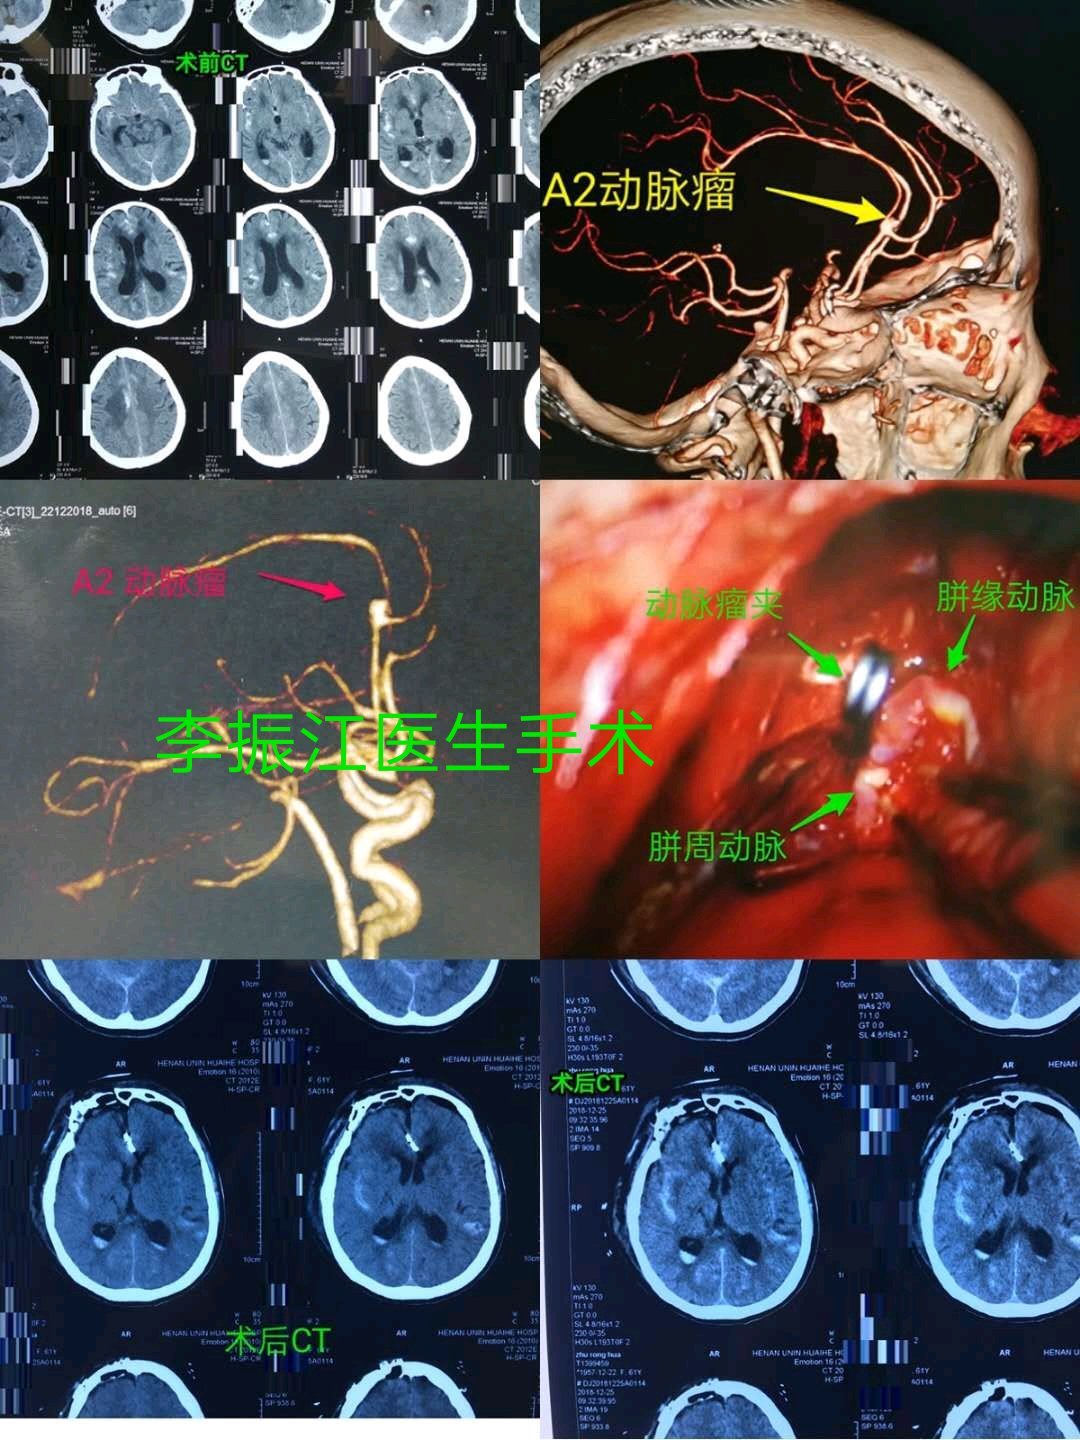

大脑前A2段动脉瘤微创手术治疗

【典型病例】女性病人,61岁,突发头疼呕吐为主诉入院,头颅CTA显示右侧大脑前A2段动脉瘤,当日

下午急诊全麻下行额下纵裂入路动脉瘤夹闭术,显微镜下操作50分钟顺利完成栽瘤动脉的暴露,分离,夹闭,术后清醒,复查头颅CT无出血及梗塞;天气转冷,脑血管病高发期,高血压病人注意按时服药,突发头疼,恶心伴意识障碍请及时到神经外科就诊!